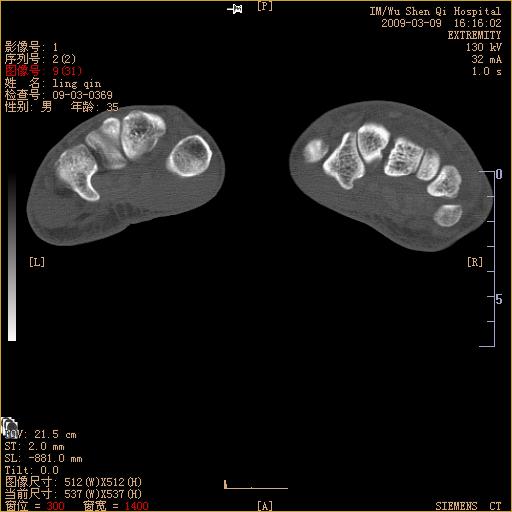

标题: CT18570:右手外伤10余天

请上传x线平片。舟状骨骨折可能大。

腕部有骨折、脱位,骨科面对ct片如何采取措施?三维一下。

请上传x线平片,腕骨多骨骨折

舟状骨骨折。

左侧舟骨及桡骨茎突骨折,第一掌骨基底部好像也有骨折,建议上传平片